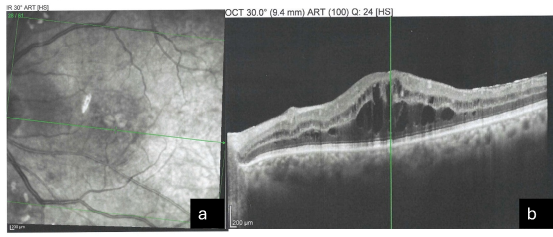

All five patients who developed ME were initially treated with topical non-steroidal anti-inflammatory drugs (NSAIDs) and topical corticosteroids. Four patients demonstrated complete resolution of ME within an average period of three to four weeks, as evidenced by normalization of CMT and resolution of cystic intraretinal changes on OCT. One patient exhibited persistent ME and required intravitreal injection therapy, after which significant anatomical and functional improvement was observed. Figure 1a and 1b show the OCT images of ME after capsulotomy.

Figure 1a and 1b: OCT Images after Capsulotomy with ME.